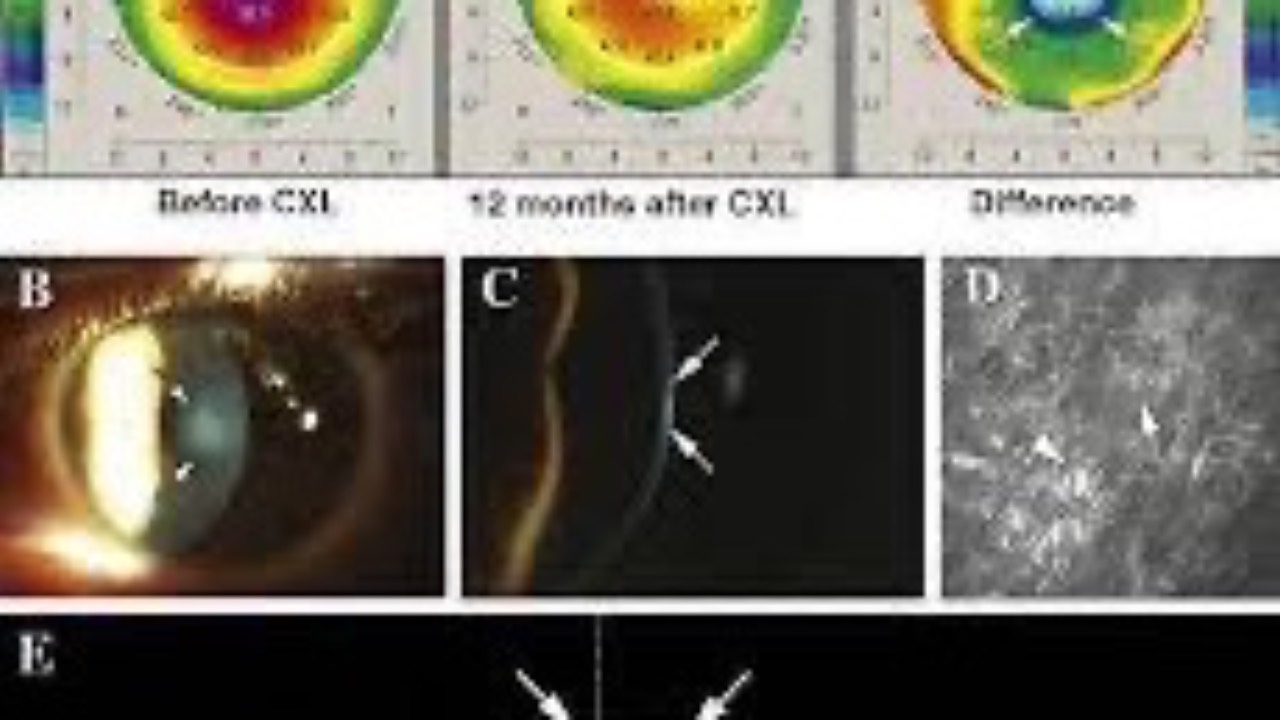

Keratoconus Podcast 2024 Update

Happy Thanksgiving Everyone!

Here is a complementary link to access the EyeX Keratoconus Podcast 2024 Update.

FREE Bonus Episode: Listen to the latest advances and treatment options for Keratoconus in 2024 (16:10 Audio Only).

SIGN ON & LISTEN